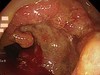

▲患者因右側下背、臀部、大腿後側疼痛,導致步態跛行。(圖/亞洲大學附屬醫院提供)

亞洲大學附屬醫院中醫科主治醫師吳俊昌表示,梁奶奶因右側下背、臀部、大腿後側疼痛,導致步態跛行,走路時無法以右腿承重,久坐時右臀部除了疼痛外,更有針刺感,故只能側身將力量放在左臀部,睡覺時更無法伸直大腿,僅能彎曲睡覺且無法翻身,故經常失眠,自述疼痛指數高達7至8分,令她苦不堪言。